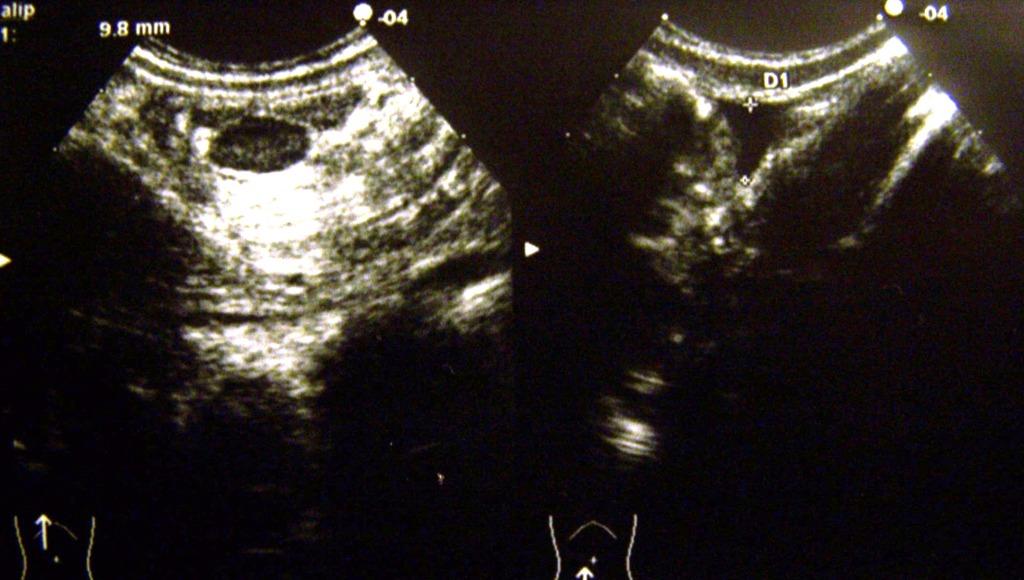

L�ecografia dell�addome si esegue con qualche difficolt� per la scarsa collaborazione della piccola. Il quadro ecografico � il seguente: pancreas, reni, fegato e milza nella norma per ecostruttura ecogenicit� e dimensioni. Vescica semivuota. Peristalsi intestinale vivace a sx, assente a destra ove si evidenzia, fra il margine inferiore del fegato e il rene, una grossa formazione con forma a bersaglio in scansione traversa all�asse principale, e forma reniforme in scansione longitudinale. La �massa� presenta pareti ispessite, prevalentemente iperecogene al centro, ipoecogene in periferia e discreta vascolarizzazione sia all�interno che all�esterno. Nel contesto della massa si evidenziano due-tre linfonodi ipoecogeni di volume lievemente aumentato con � max di mm 6. A sinistra le anse intestinali sono regolari (Figura 1).

Figura 1. Scansione ecografica longitudinale ( a sx) e traversa (a dx) prima del clisma di acqua